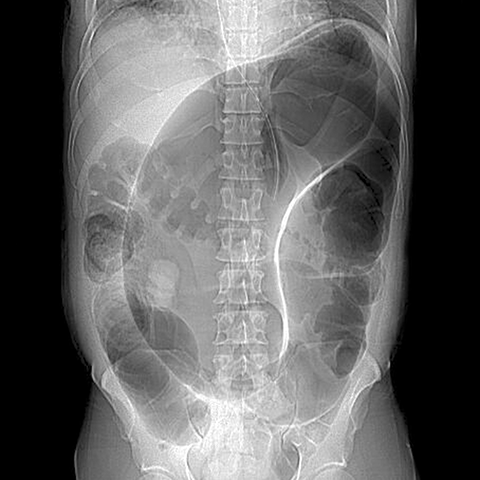

Sigmoid Volvulus, film [2 of 2]